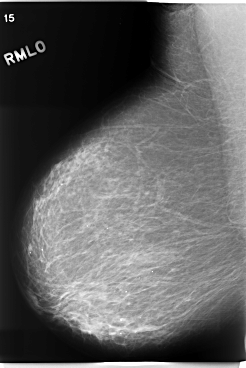

C_0205_1.RIGHT_MLO

RIGHT_CC LINES 5888 PIXELS_PER_LINE 3552 BITS_PER_PIXEL 12 RESOLUTION 50 NON_OVERLAY

RIGHT_MLO LINES 5880 PIXELS_PER_LINE 3936 BITS_PER_PIXEL 12 RESOLUTION 50 NON_OVERLAY